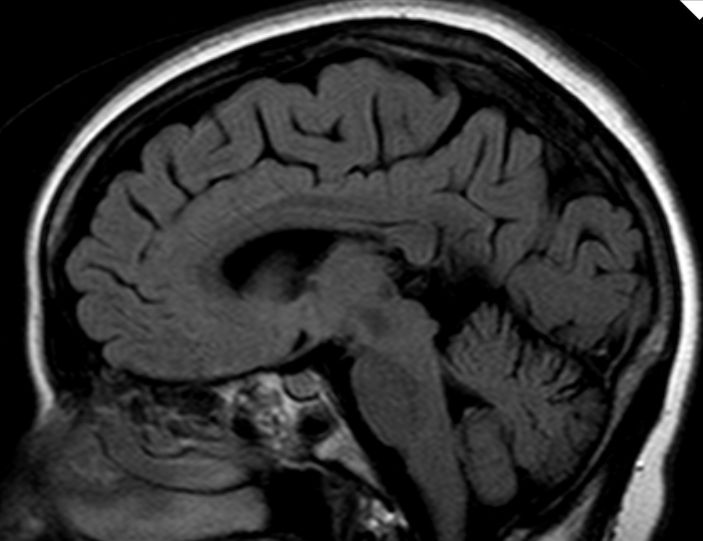

Frontobasis-Tumor

50-jährige Frau (I251), die vor 7 Jahre ein Mammakarzinom (rechts oben außen, T1c No Mo, invasiv NST hatte. Bisher metastasenfrei. Jetzt vor der Sella, in der linken Keilbeinhöhle eine z.T. verkalkte Raumforderung. 2 Jahre unverändert kontrolliert.